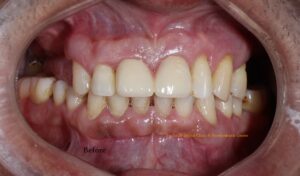

A 50-year-old male patient from New Zealand arrived at our clinic seeking to replace his upper teeth. He had recently returned to Nepal for a 20-day visit and had already explored treatment options at other dental facilities. Unsatisfied with both the proposed treatment plans and the costs, he came to us with his desires and expectations. We listened attentively, taking careful note of his needs. He had already had X-rays taken at the request of a previous dentist.

On his first visit, we performed a thorough examination of his teeth and gums. He had upper back teeth missing and remaining upper front teeth were mobile, whereas his lower teeth were not mobile but required gums treatment. We explained his condition of oral hygiene and treatment required. We presented him with all available options, including removable and fixed prostheses. He opted for a fixed prosthesis with upper arch replacement using 4 dental implants (All-on-4). We also discussed different implant brands and types, and he selected Bredent Copasky implants (Fast & Fixed). Additionally, we offered various prosthetic options for permanent prosthesis, and he chose a hybrid denture.

Fig: Pre-operative extra-oral, intra-oral photographs and X-ray